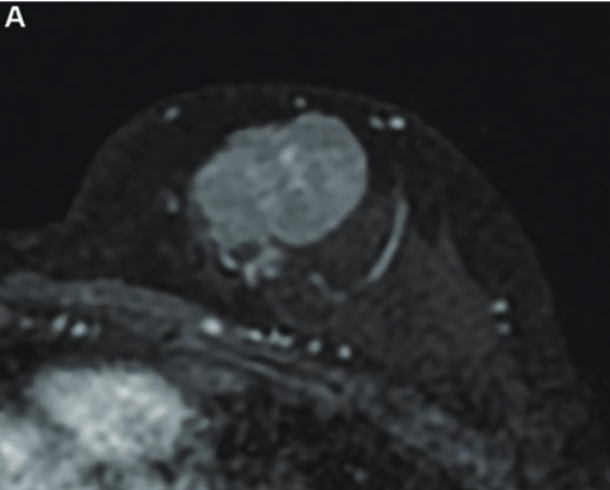

The therapy contains actinium-225 (Ac-225), which works by passing through the blood to stick to cancer cells without harming healthy surrounding tissues.

The study is evaluating the potential of Ac-225 alone and with the immunotherapy drug pembrolizumab in women with ER+, HER2-negative, unresectable or metastatic breast cancer expressing somatostatin receptors.